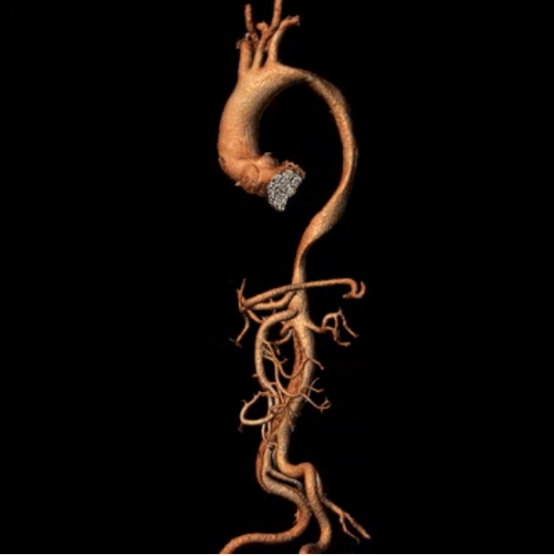

2025-04-29五院技术 | 家中顶梁柱遭遇"血管炸弹", 心脏中心2小时“绣花般”拆解危机

“医生,我的身体好像被撕开了!”38岁的庄先生被急救推床送入广医五院时,胸背部爆发的撕裂性剧痛已让他几近休克。监护仪显示血压呈“断崖式”下降,患者面色惨白、冷汗浸透衣衫,CT血管造影…